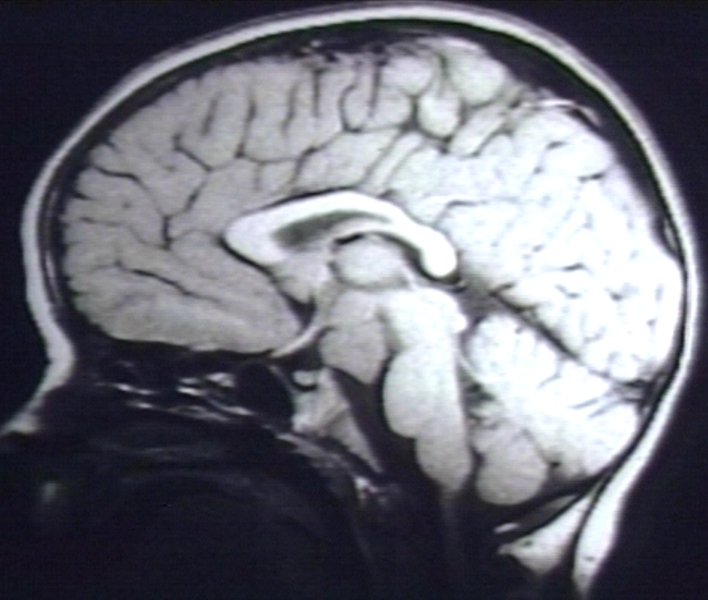

RADIOLOGY: NERVOUS: BRAIN: HAMARTOMA, HYPOTHALAMUS; T1 WO (MRI)